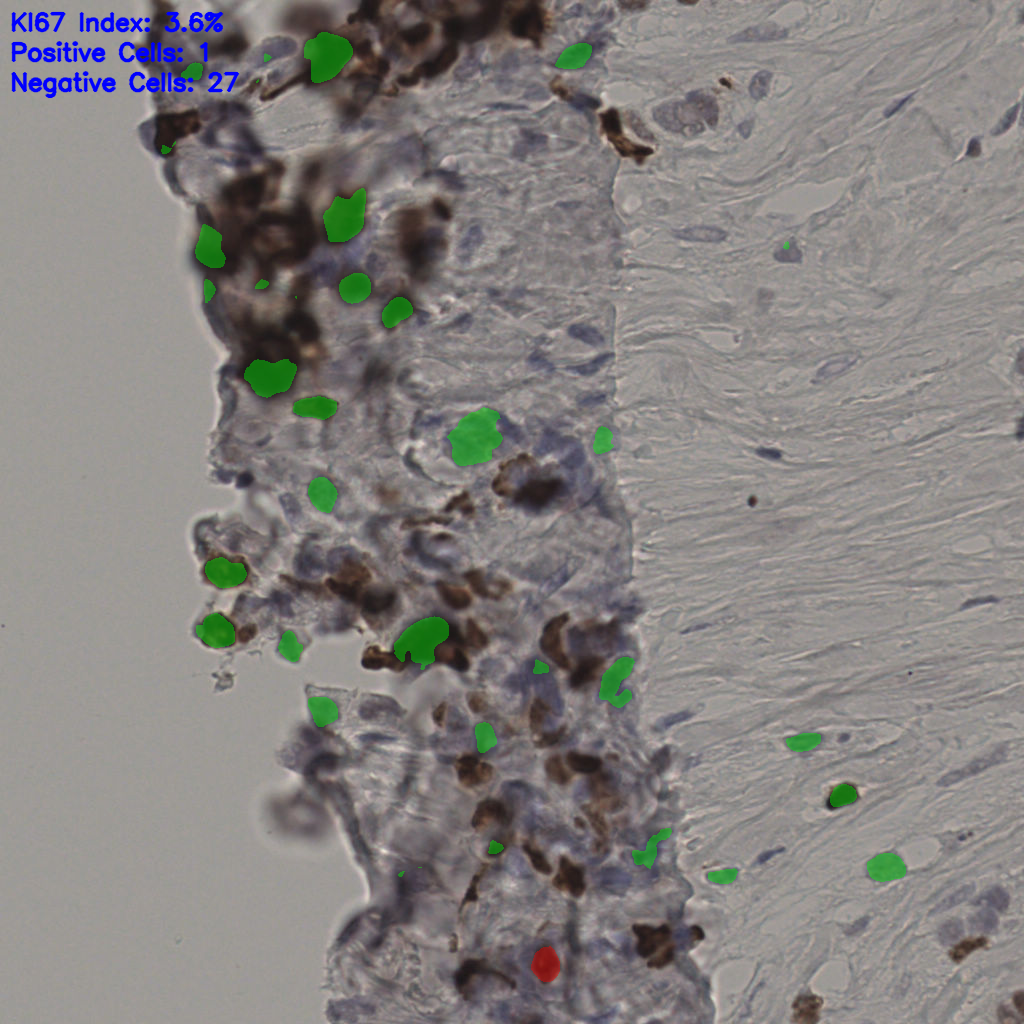

17.75%

Ki67 指数

阴 7986 阳 1723

总切片 2640

有效 412

已标记 412

有效率 16%